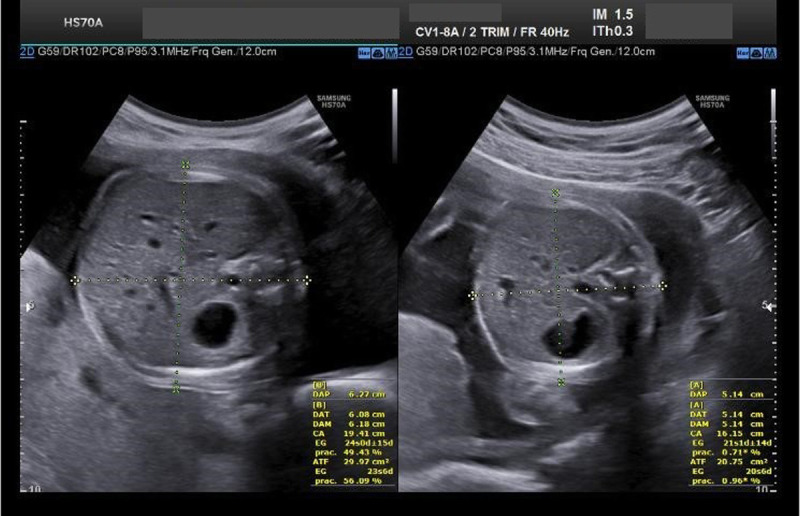

Selective fetal growth restriction (sFGR) is a severe condition that complicates 10% to 15% of all monochorionic diamniotic (MCDA) twin pregnancies. Pregnancies complicated with sFGR are at high risk of intrauterine demise or adverse perinatal outcome for the twins. Three clinical types have been described according to the umbilical artery (UA) Doppler pattern observed in the smaller twin: type I, when the UA Doppler is normal; type II, when there is persistent absent or reversed end-diastolic blood flow in the UA Doppler; and type III, when there is intermittent absent and/or reversed end-diastolic blood flow in the UA Doppler. Clinical evolution and management options mainly depend on the type of sFGR. Type I is usually associated with a good prognosis and is managed conservatively. There is no consensus on the management of types II and III, but in earlier and more severe presentations, fetal interventions such as selective laser photocoagulation of placental anastomoses or selective fetal cord occlusion of the smaller twin may be considered. This review aims to provide updated information about the diagnosis, evaluation, follow-up, and management of sFGR in MCDA twin pregnancies.